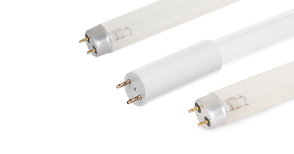

Негатоскоп общего назначения Армед 1-кадровый – компактный медицинский прибор для быстрого просмотра одного рентгеновского снимка, оборудованный светодиодным источником освещения. Внутри корпуса установлены LED-линейки, которые обеспечивают необходимую яркость свечения. Смотровой экран из молочного акрилового стекла равномерно рассеивает свет по всей площади. Сухие рентгенограммы легко устанавливаются в пазы экрана для удобного просмотра.